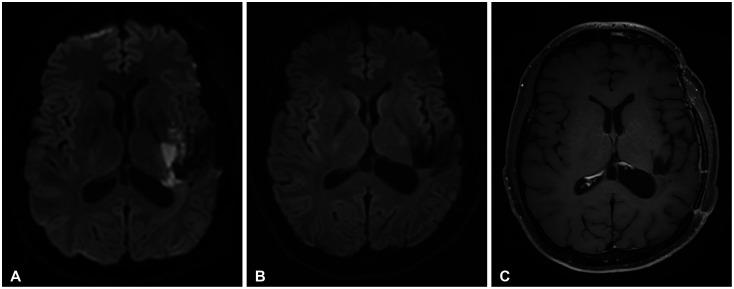

低级别胶质瘤的高级别转化长期以来一直是治疗过程中预后不良的因素。2016年,世界卫生组织(WHO)中枢神经系统(CNS)肿瘤分类在弥漫性星形细胞瘤分类中采用了异柠檬酸脱氢酶(IDH)突变状态。2021年的分类将胶质母细胞瘤定义为IDH野生型,将IDH突变型星形细胞瘤分为2级、3级或4级。肥胖细胞形态、大部分残留肿瘤、患者年龄以及放疗后的复发此前被提及为低级别胶质瘤高级别转化的危险因素。我们报告一名34岁男性患者,根据2021年WHO中枢神经系统肿瘤分类最初被诊断为IDH突变型2级星形细胞瘤。由于首次手术切除在术后MRI上实现了大体全切,未给予辅助治疗并计划进行定期随访。在1年的随访MRI检查中,在紧邻手术切除腔的同侧脑实质出现了两个新的强化结节性病变。挽救性开颅手术实现了大体全切,病理诊断为IDH突变型WHO 4级星形细胞瘤。我们根据先前的WHO分类描述该肿瘤,以评估高级别转化的风险,并讨论导致低级别星形细胞瘤高级别转化的可能危险因素。